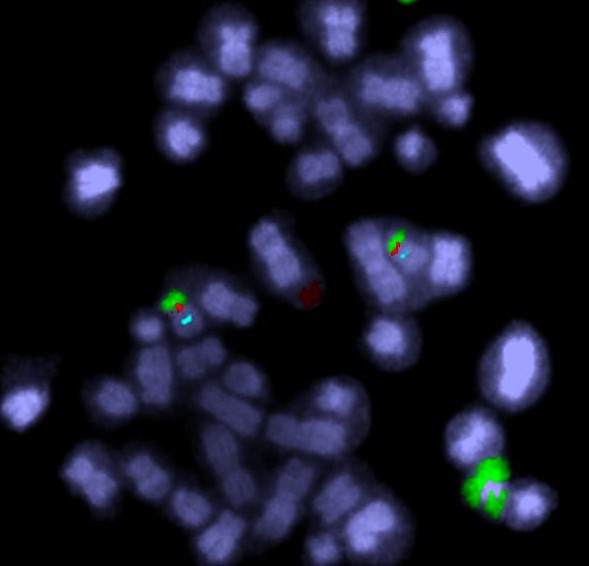

Coloured pieces of DNA can be made to attach to the chromosome – this shows where that DNA is in the chromosome.